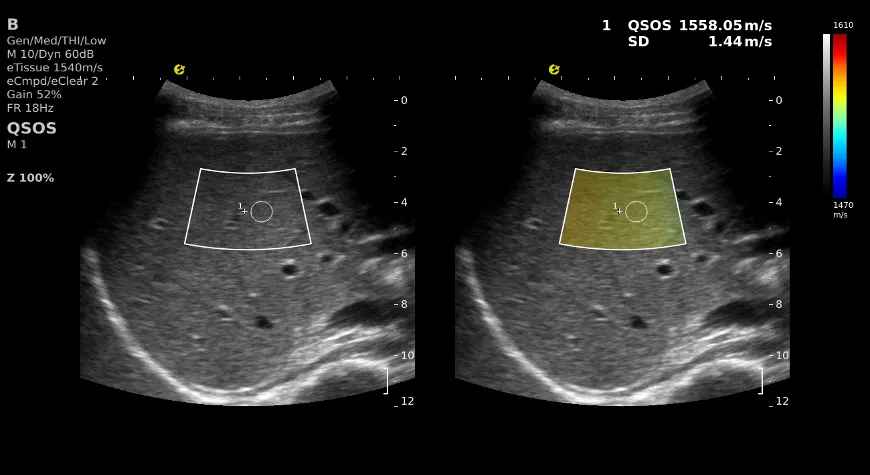

肝脏QSOS图像

在肝脏的超声诊断中,QSOS?不仅能够提供比传统超声更加详细的图像和丰富的参数,还能通过颜色编码的方式,直观地展示出不同部位的声速值,帮助医生快速识别病变区域,使早期的肝纤维化、脂肪肝等病变无所遁形

QSOS?就像是给你的肝脏拍了一张“彩色照片”,不仅让每一个细节都清晰可见,而且还可以标识出不同区域声速的大小,让医生一目了然,快速做出诊断。